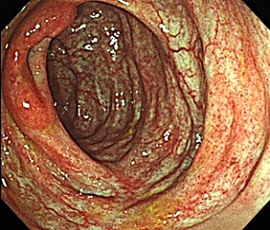

約6年前より繰り返す右側腹部痛と下痢を主訴にて精査目的に受診。腹部レントゲン検査にて、右側結腸の腸間膜側に一致した石灰化を認め、精査の結果、典型的な結腸辺縁静脈の石灰化と診断。手術(腹腔鏡下結腸切除術)を施行した。病理診断結果は、静脈硬化性大腸炎であった。

内視鏡画像